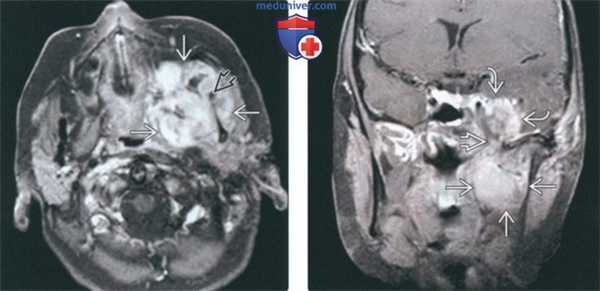

(Слева) КТ в костном окне, аксиальная проекция. Типичная хондросаркома височно-нижнечелюстного сустава низкой степени злокачественности. Определяются небольшие кальцификаты дистрофической природы (либо кальцифицированный матрикс самого образования) и обширная деарукция/ремоделирова -ние суставной ямки.

(Справа) MPT Т2ВИ в аксиальной проекции, тот же пациент. Определяется дольчатое гиперинтенсивное образование с четкими контурами, которое окружает мыщелок нижней челюсти.

(Слева) На корональной КТ с КУ визуализируется обызвествленная опухоль в жевательном пространаве, распроараняющаяся через основание черепа. Картина обызвеавления характерна для высокодифференцированной хондросаркомы.

(Справа) На аксиальной MPT (Т1 ВИ) визуализируется опухоль с промежуточным сигналом вокруг ветви нижней челюсти справа. В данном случае картина хондросаркомы жевательного пространства неспецифична.